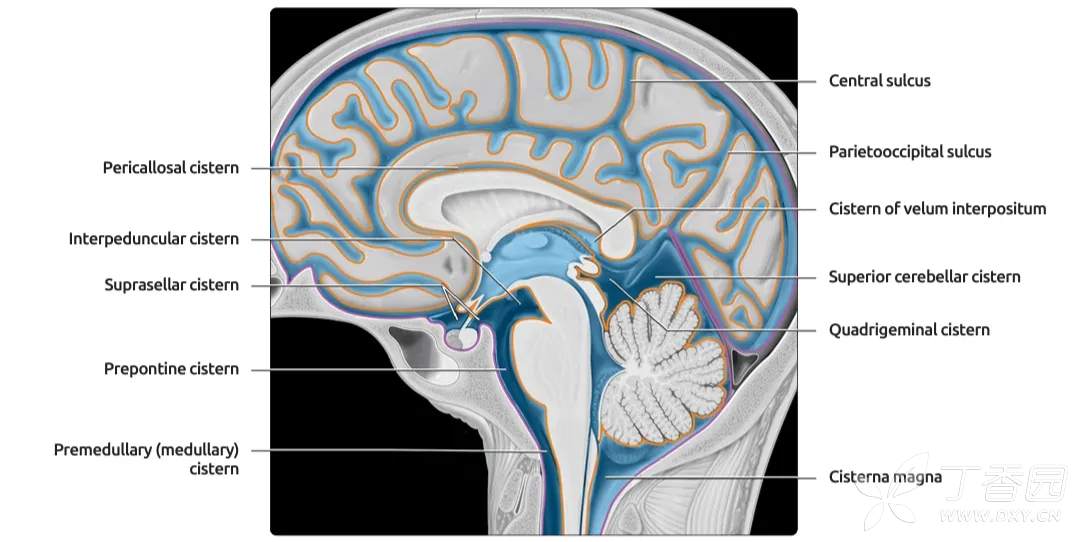

重要的脑池有:

由于脑池和脑室内均为低密度的脑脊液,有时影像上二者易于混淆。因此,熟悉脑池的断层影像解剖,对病变的影像学定位诊断至关重要。MRI 可较好地显示脑池及内含结构。CT 平扫即可观察较低密度的脑池。

四叠体池

四叠体池 quadrigeminal corpus cistern 又称上池 superior cistern ,居中脑四叠体后面与小脑蚓部前缘之间,两端向外连于环池翼部,向前外通环池本部。四叠体池和环池位于小脑幕切迹内,幕上或幕下的病变可经这些脑池延伸。例如,小脑幕切迹疝可使这些脑池变窄或消失。

小脑上池

小脑上池 superior cerebellar cistern 一般见于颅盖下部较低层面,为四叠体池向后的延续,位于小脑幕与小脑上面之间,以矢状断面显示较佳。

环池

环池 ambience cistern 分本部和翼部。

环池本部围绕中脑大脑脚两侧,连接于四叠体池和脚间池之间。

翼部向外伸向丘枕后下方,又名丘脑后池。

环池内有大脑后动脉、小脑上动脉、脉络丛前动脉和后动脉、基底静脉和滑车神经。

由四叠体池、环池和脚间池可勾画出中脑的轮廓。

鞍上池

鞍上池 suprasellar cistern 为CT 和MRI 等影像学用语。鞍上池位于蝶鞍上方,是交叉池、脚间池或桥池在轴位扫描时的共同显影。

1. 交叉池 chiasmatic cistern 位于视交叉周围,外界是颈内动脉,前方有大脑前动脉和前交通动脉。

2. 脚间池 interpeduncular cistern 位于视交叉后方、脚间窝前方,内有动眼神经、大脑后动脉水平段等。

3. 桥池 pontine cistern 位于斜坡与脑桥基底部之间,内有基底动脉,向两侧与脑桥小脑角池延续。